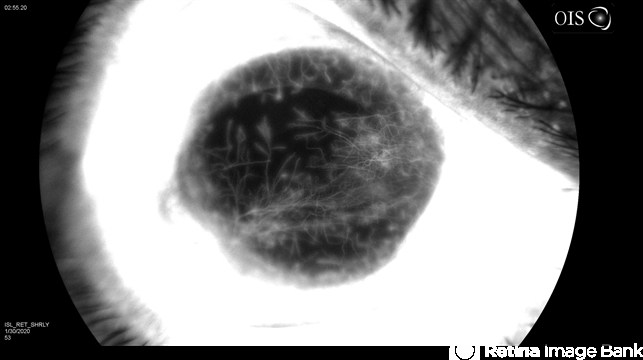

- cornea, fluorescein angiogram (FA), phthisical cornea, corneal vascularization, diabetes

- 44-year-old white female with type 1 diabetes, and phthisical OD, fluorescein angiogram of heavily vascularized corneal surface at 35 deg, flash at 100 watts, on anterior external settings.